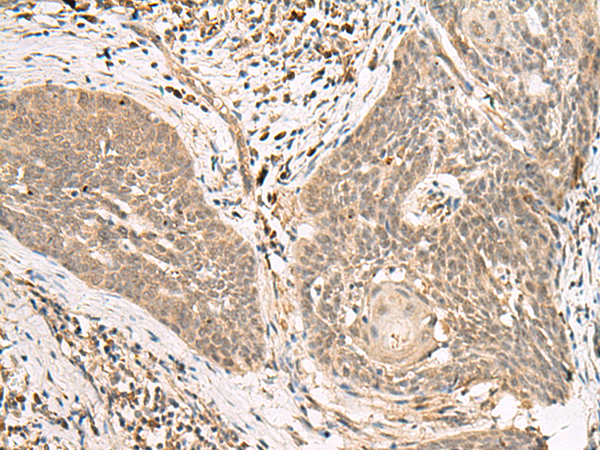

分类: 科研抗体货号: P13527别名: GPHR; GPR89; SH120; GPR89B; GPR89C; UNQ192应用: WB,IHC反应种属: Human, Mouse